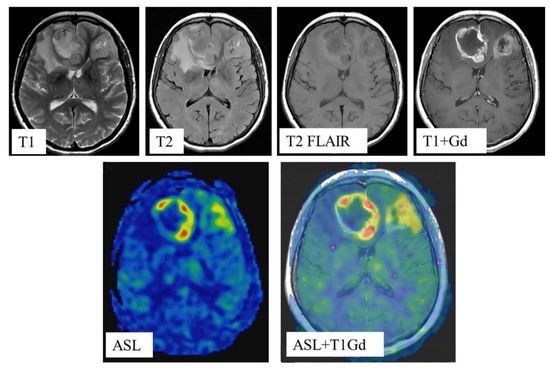

In all cases, blood flow maps were fused with anatomical images (T2, T2-FLAIR, enhanced T1) using the NeuroRegistration program (GE Healthcare)—Figure 2.

Figure 2.

MRI scans and quantitative CBF maps of anterofrontal region IDH1-wildtype glioblastoma. ASL perfusion showed high TBF values (247.2 mL/100 g/min).